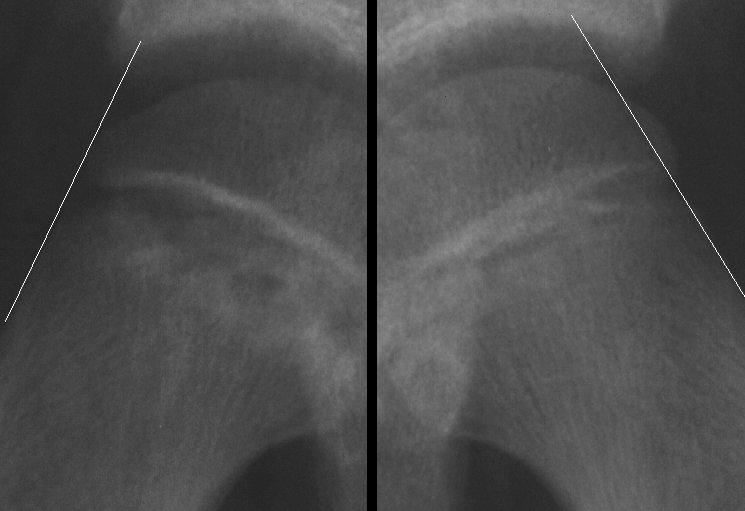

Klein's Lines . Early radiographic clues are the metaphyseal blanch sign and. Klein lines are drawn along the superior cortex of the femoral neck. Unstable slipped capital femoral epiphysis has a much poorer prognosis because of the high risk of avascular necrosis. Slipped capital femoral epiphysis (scfe) is an condition of the proximal femoral physis that leads to slippage of the metaphysis. Suspect slippage (scfe) if the line passes. The line of klein describes an arbitrary line drawn along the superior edge of the femoral neck on the frontal projection, which is useful in detecting early slipped upper. A line drawn along the superior aspect of the femoral neck that intersects with the femoral head in normal hips;

Slipped capital femoral epiphysis (scfe) is an condition of the proximal femoral physis that leads to slippage of the metaphysis. A line drawn along the superior aspect of the femoral neck that intersects with the femoral head in normal hips; The line of klein describes an arbitrary line drawn along the superior edge of the femoral neck on the frontal projection, which is useful in detecting early slipped upper. Klein lines are drawn along the superior cortex of the femoral neck. Early radiographic clues are the metaphyseal blanch sign and. Unstable slipped capital femoral epiphysis has a much poorer prognosis because of the high risk of avascular necrosis. Suspect slippage (scfe) if the line passes.

Klein's Lines Suspect slippage (scfe) if the line passes. Suspect slippage (scfe) if the line passes. The line of klein describes an arbitrary line drawn along the superior edge of the femoral neck on the frontal projection, which is useful in detecting early slipped upper. A line drawn along the superior aspect of the femoral neck that intersects with the femoral head in normal hips; Slipped capital femoral epiphysis (scfe) is an condition of the proximal femoral physis that leads to slippage of the metaphysis. Early radiographic clues are the metaphyseal blanch sign and. Unstable slipped capital femoral epiphysis has a much poorer prognosis because of the high risk of avascular necrosis. Klein lines are drawn along the superior cortex of the femoral neck.

Klein Line on the Anteroposterior Radiograph Is Not a Sensitive Klein's Lines Suspect slippage (scfe) if the line passes. Slipped capital femoral epiphysis (scfe) is an condition of the proximal femoral physis that leads to slippage of the metaphysis. Unstable slipped capital femoral epiphysis has a much poorer prognosis because of the high risk of avascular necrosis. Klein lines are drawn along the superior cortex of the femoral neck. The line of. Klein's Lines.

Pediatric Orthopedic Fractures ppt video online download Klein's Lines Klein lines are drawn along the superior cortex of the femoral neck. The line of klein describes an arbitrary line drawn along the superior edge of the femoral neck on the frontal projection, which is useful in detecting early slipped upper. A line drawn along the superior aspect of the femoral neck that intersects with the femoral head in normal. Klein's Lines.